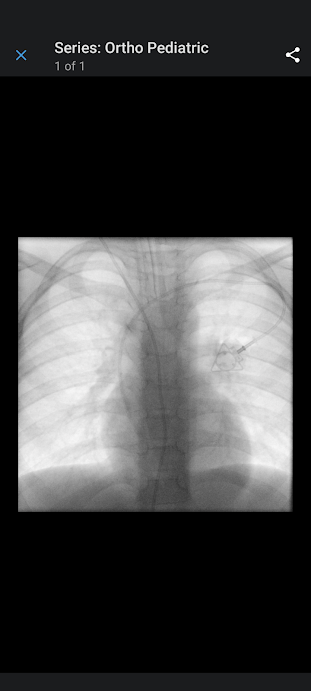

Tube on the left is his shunt. The triangle is the power port.

And here we are, at the end of the day. Nurse was flushing his port, getting ready for Chemo.

This is just so immeasurably hard. Please pray now that the treatments work for him. The nurses have been awesome. Conner is getting a combination of Vincristine and Carboplatin. He is getting a low dose, and he gets anti-nausea meds before he starts. He had no side effects this time. We will see how his body tolerates it over the course of the next year (if we have to go for that long, but we already have appointments booked into may). I am hopeful that he will continue to do well with it. Praying the chemo shrinks his tumor. Our next appointment is next Wednesday and we will be going weekly to Rochester.